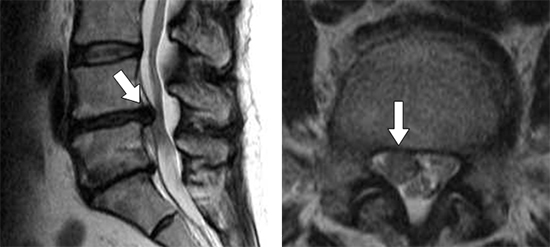

腰椎椎間板ヘルニアのMRI写真の図

図1 腰椎椎間板ヘルニアのMRI写真

左:縦断面像。右:横断面像。変性した椎間板(矢印)が後方に脱出し、脊髄神経を圧迫している。